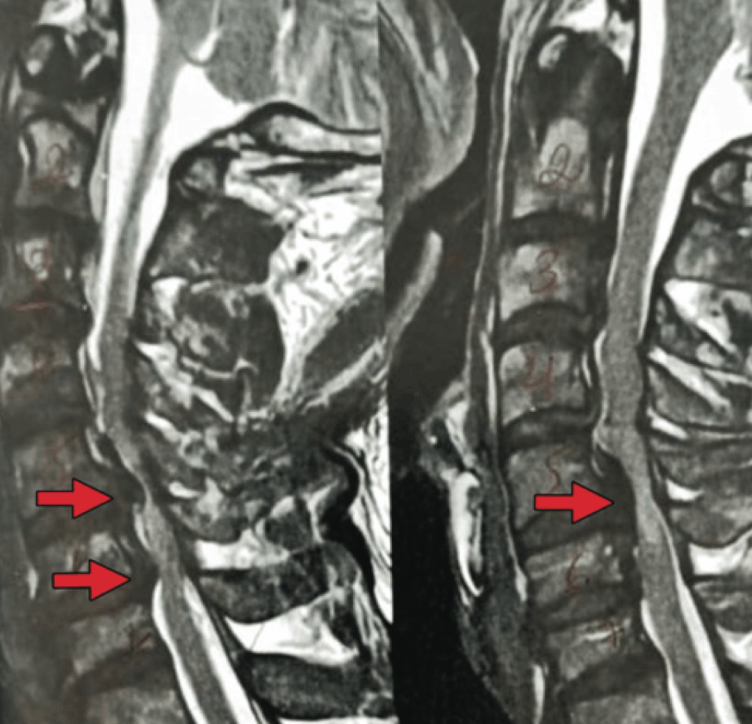

A síndrome de Bow Hunter se manifesta quando a artéria vertebral é comprimida após a rotação da cabeça. A compressão sintomática com estenose da artéria vertebral devido a osteófitos cervicais é uma causa rara e ocorre devido a um processo degenerativo progressivo. Geralmente, a compressão se origina anteromedialmente do processo uncinado e é assintomática devido à competência da artéria vertebral contralateral.

No paciente descrito, a compressão se apresentou superomedialmente devido a osteófitos na faceta articular superior da vértebra C5, e a artéria vertebral contralateral estava obstruída. Uma avaliação cuidadosa com imagens, principalmente angiotomografia 3D pré-operatória, é necessária para determinar a abordagem mais benéfica para a descompressão. O tratamento de escolha para compressão sintomática induzida por espondilose cervical é a cirurgia de descompressão.